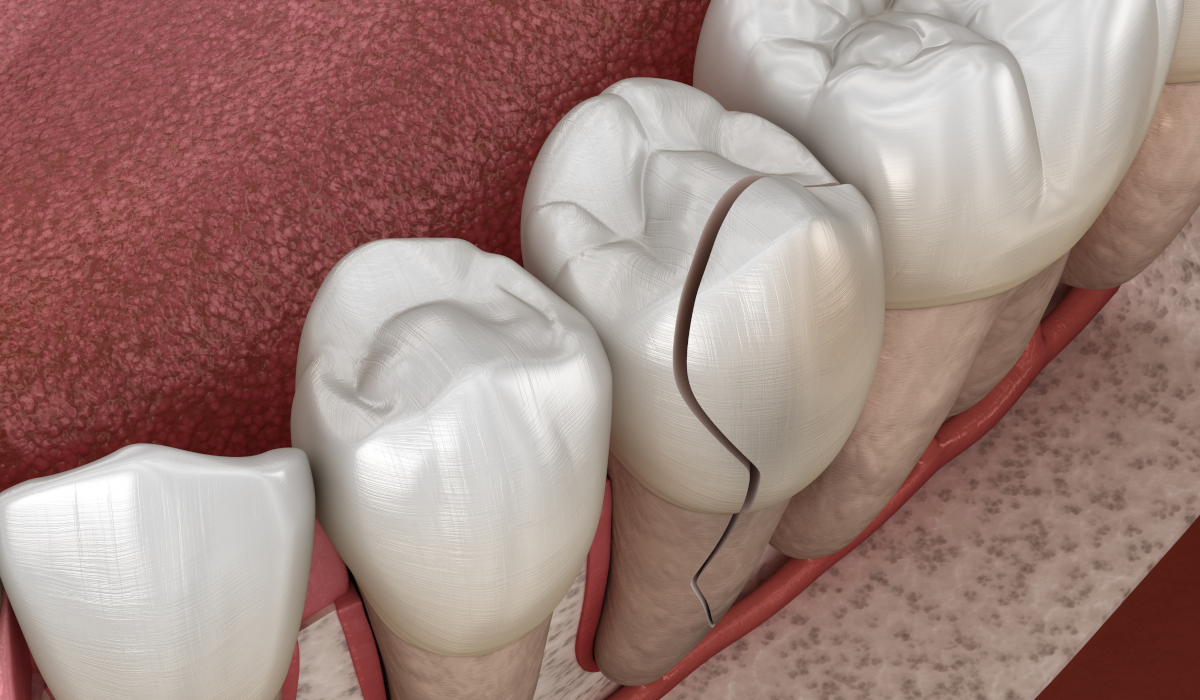

This happens quite a bit, especially when you are eating too fast or chewing gum or not paying attention while chewing. Most of the time, this trauma has pain associated with it. The best thing to do is rinse with warm water and take some over-the-counter pain medications. If the injury is deeper, please call us ASAP so that we can get you in and assess the wound. Stitches may be necessary. If there is bleeding, please apply pressure with a paper napkin until you are able to get to us.